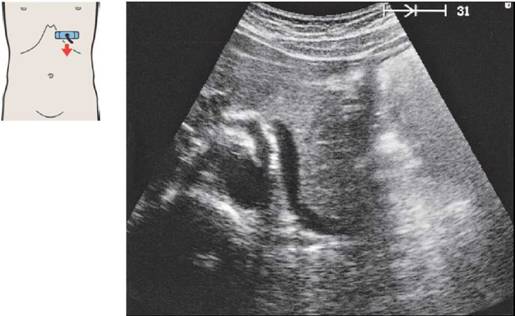

31 Артерии чревного ствола

Печеночная артерия при продольном сканировании

Место отхождения чревного ствола и его деление на ветви подвержено индивидуальным вариационным изменениям.

Печеночная артерия идет вверх и вправо и направляется вдоль нижнего края печени к ее воротам.

Продольное сканирование между аортой и нижней полой веной дает типичный вид сечения четырех сосудов: печеночной артерии, места слияния селезеночной и верхней брыжеечной вен, левой почечной вены и правой почечной артерии.

Продольное сканирование через нижнюю полую вену дает типичный вид сечения следующих сосудов: нижней полой вены, воротной вены, печеночной артерии и почечной артерии.